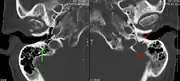

The diagnostic examination of a person with suspected multiple myeloma typically includes a skeletal survey. This is a series of X-rays of the skull, axial skeleton, and proximal long bones. Myeloma activity sometimes appears as "lytic lesions" (with local disappearance of normal bone due to resorption) or as "punched-out lesions" on the skull X-ray ("raindrop skull"). Lesions may also be sclerotic, which is seen as radiodense.[76] Overall, the radiodensity of myeloma is between −30 and 120 Hounsfield units (HU).[77] Magnetic resonance imaging is more sensitive than simple X-rays in the detection of lytic lesions, and may supersede a skeletal survey, especially when vertebral disease is suspected. Occasionally, a CT scan is performed to measure the size of soft-tissue plasmacytomas. Nuclear Medicine Bone scans are typically not of any additional value in the workup of people with myeloma (no new bone formation; lytic lesions not well visualized on nuclear bone scan).

Pathological fracture of the lumbar spine due to multiple myeloma- A CT of the brain revealed a lytic lesion in the left temporal bone (right side of image), and petrous temporal bones involving the mastoid segment of the facial nerve canal. Red arrows: lesion; green arrow: normal contralateral facial nerve canal. The lesions are consistent with a myeloma deposit.